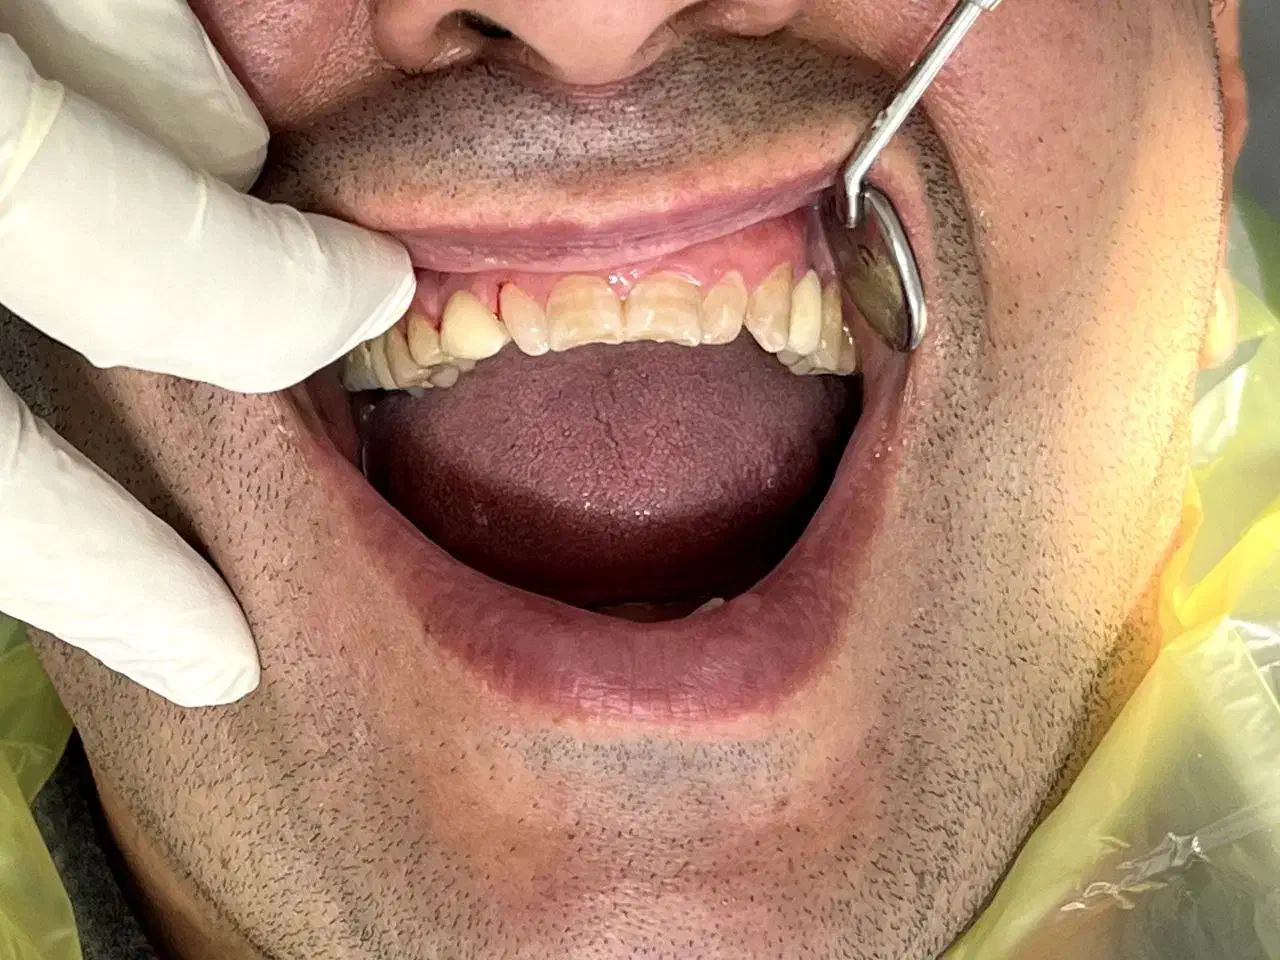

خدمات دندان پزشکی با متناسب شرایط و بودجه شما

ساعت فعالیت ۹صبح الی ۲۴ حتی روز های تعطیل و جمعه دندان پزشکی بزرگسال و اطفال با شش سال سابقه ی کاری طرف قرارداد با بیمه ی تکمیلی ( تامین اجتماعی البرز کوثر رازی ایران و معلم و دانا و آتیه سازان حافظ بانک کشاورزی و sos ) تعرفه برای مراجعین بدون بیمه تکمیلی جرم گیری ۹۰۰هزار تومان الی یک میلیون و دویست کشیدن ساده ۴۰۰الی ۷۰۰هزار تومان کشیدن دندان عقل ۹۰۰هزار تومان جراحی دندان ۱۶۰۰الی۱۸۰۰ جراحی دندان عقل ۱۸۰۰ الی ۲ ترمیم ۱۵۰۰ الی ۱۷۰۰ کامپوزیت ونیر از ۱۵۰۰ عصب کشی و ترمیم دندان ۲۷۰۰الی۳۹۰۰ روکش های معمولی ۳۴۰۰ روکش های سرامیک ۴۳۰۰ ایمپلنت با روکش ۱۵الی ۱۷میلیون کلیه خدمات دندان پزشکی مخصوص اطفال (عصب کشی ترمیم کشیدن جرم گیری روکش) شرایط اقساطی با دریافت چک صیاد امکان پذیر میباشد ادرس رشت گاز دروازه لاکان مسجد امیرالمومنین کوچه ی ۱۶متری سمیه جهت نوبت دهی در دیوار خدماتی ک درخواست دارین رو به همراه شماره تماس ارسال بفرمایید همه روزه حتی روز های تعطیل